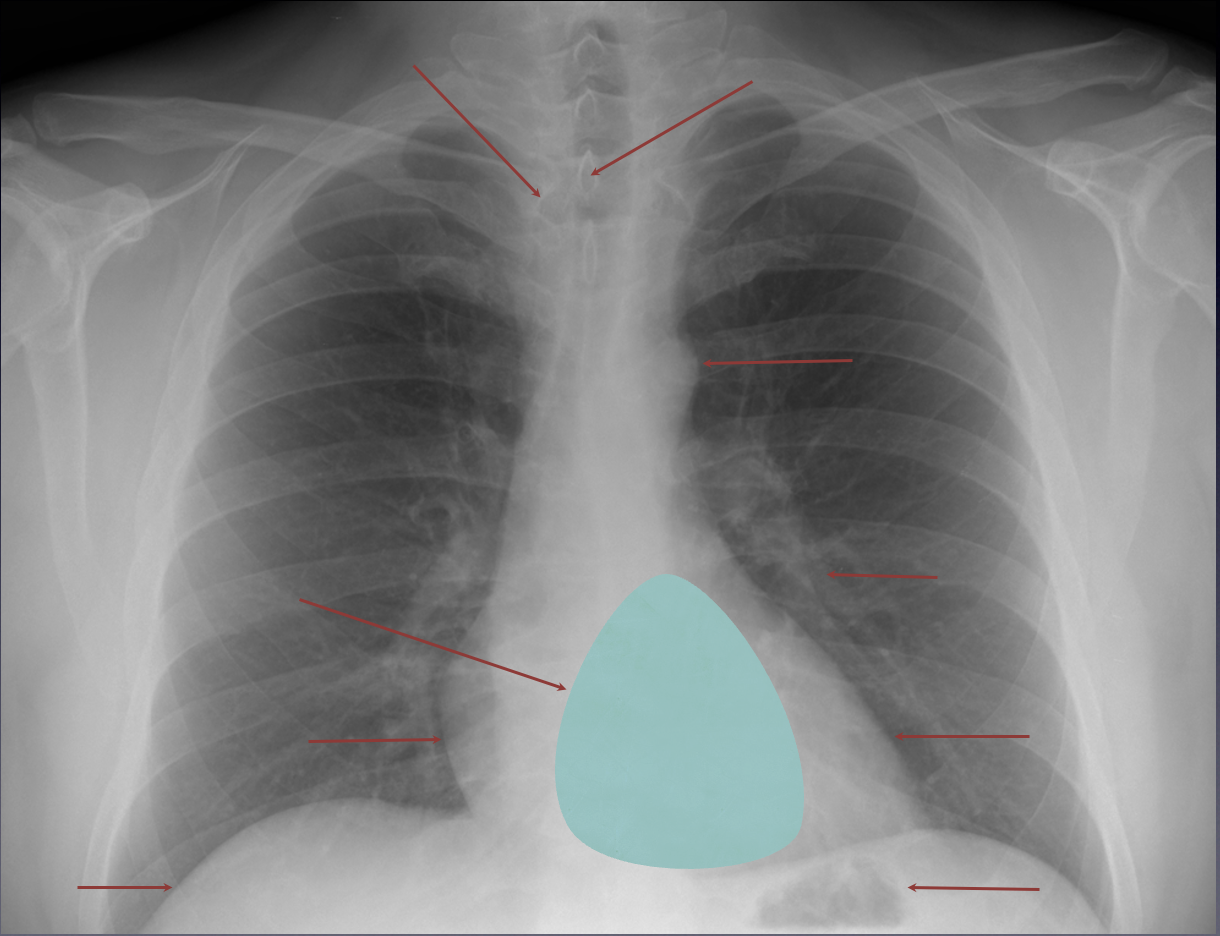

Which lobe is which ?

Red: right upper lobe (RUL)

Green: right middle lobe (RML)

Purple: right lower lobe (RLL)

Yellow: left upper lobe (LUL)

Blue: left lower lobe (LLL)